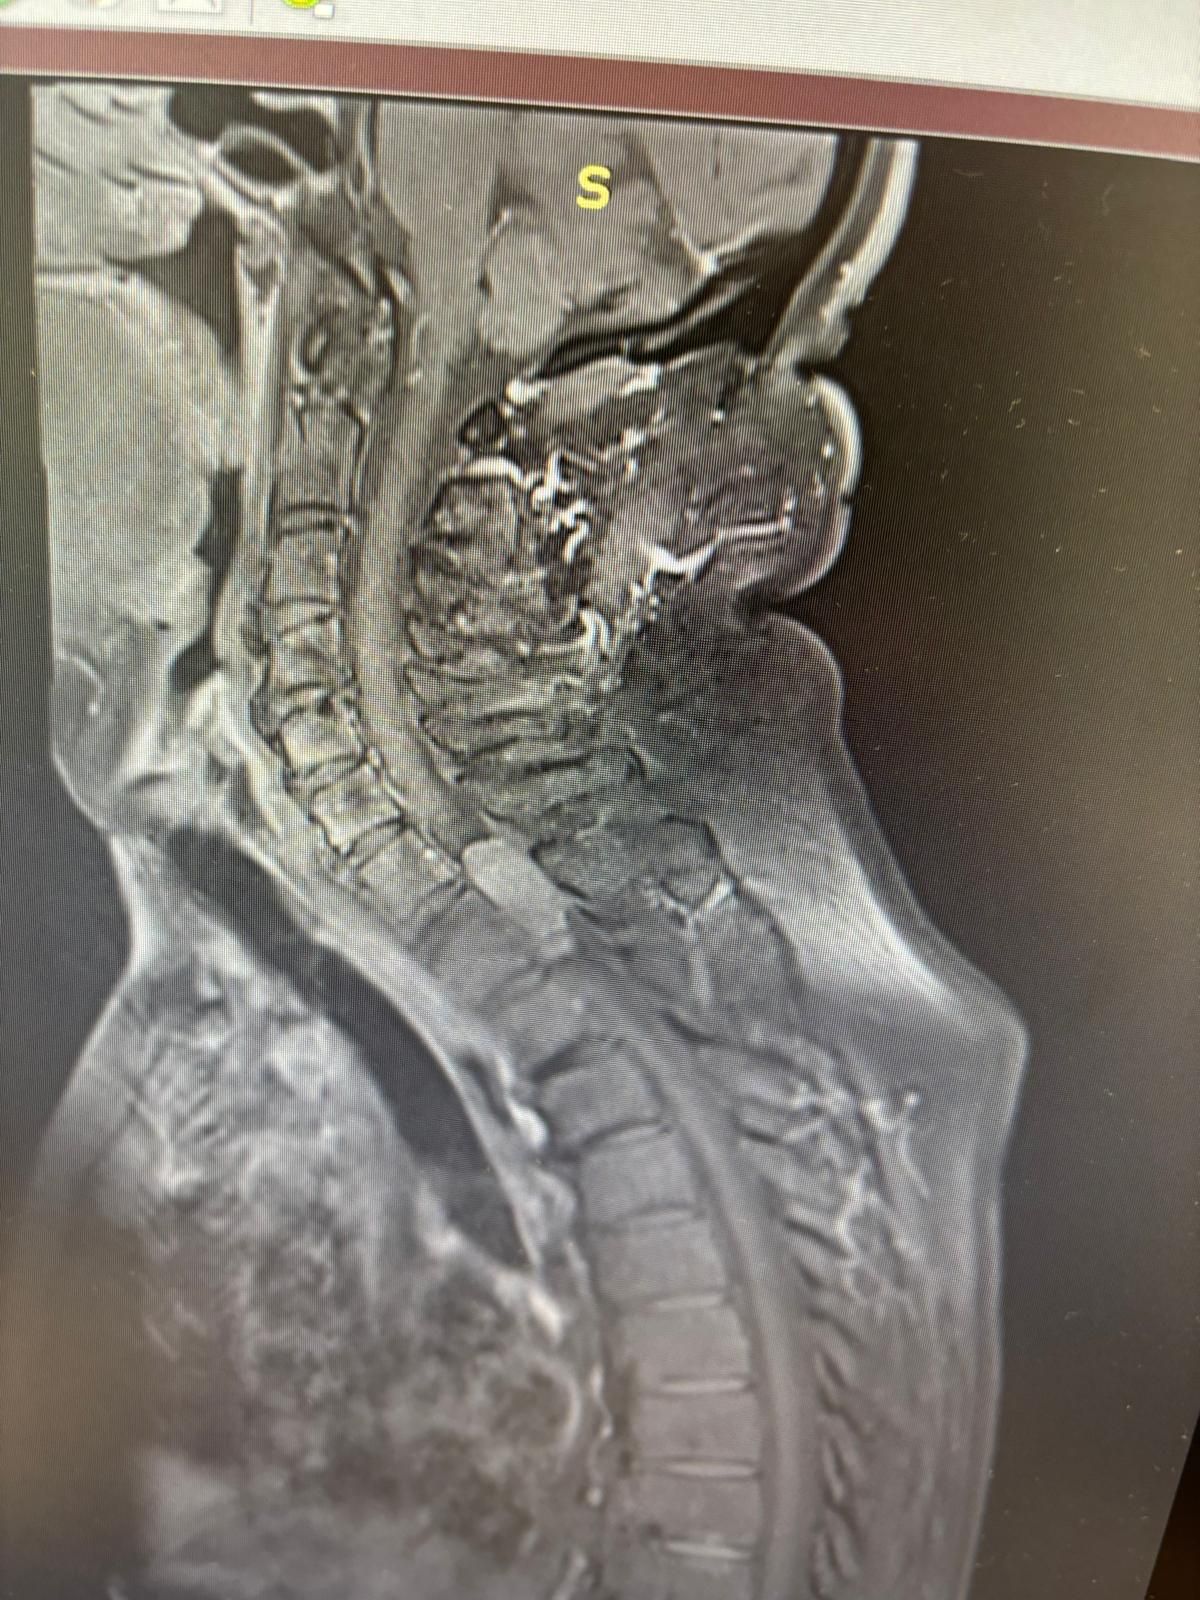

Foto e video